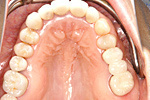

症例 14

① 前歯1本が無い状態です。通常は前後の2本の歯を削ってブリッジにしますが、インプラントをすることにより、健康な歯を削る必要はなくなります。

② インプラントが埋め込まれて安定した状態です。

③ インプラントに固定式の歯が入ったところです。健康な自分の歯を守る事ができました。

20才代 女性

総額:42万円(税別)

リスク副作用:顎骨の変化により、自分の歯との間に隙間や段差が生じることがあります。